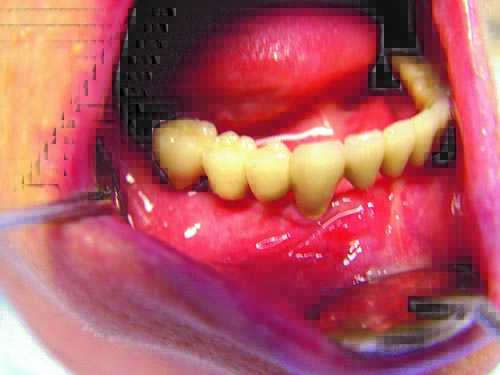

Another clinical case using the two-stage method.The patient is a 34-year old woman.

The previous treatment restoration over the period of 1989-1998.

![/userfiles/files/kniga29%281%29.jpg [/userfiles/files/kniga29%281%29.jpg]](/userfiles/files/kniga29%281%29.jpg)

A heavy smoker who lost her own teeth, as well as the intraosseous implants on the left side of the mandible. An x-ray illustrating the treatment.

![/userfiles/files/kniga30.jpg [/userfiles/files/kniga30.jpg]](/userfiles/files/kniga30.jpg)

View of the mandible with a metaloceramic bridge fixed in 1998.